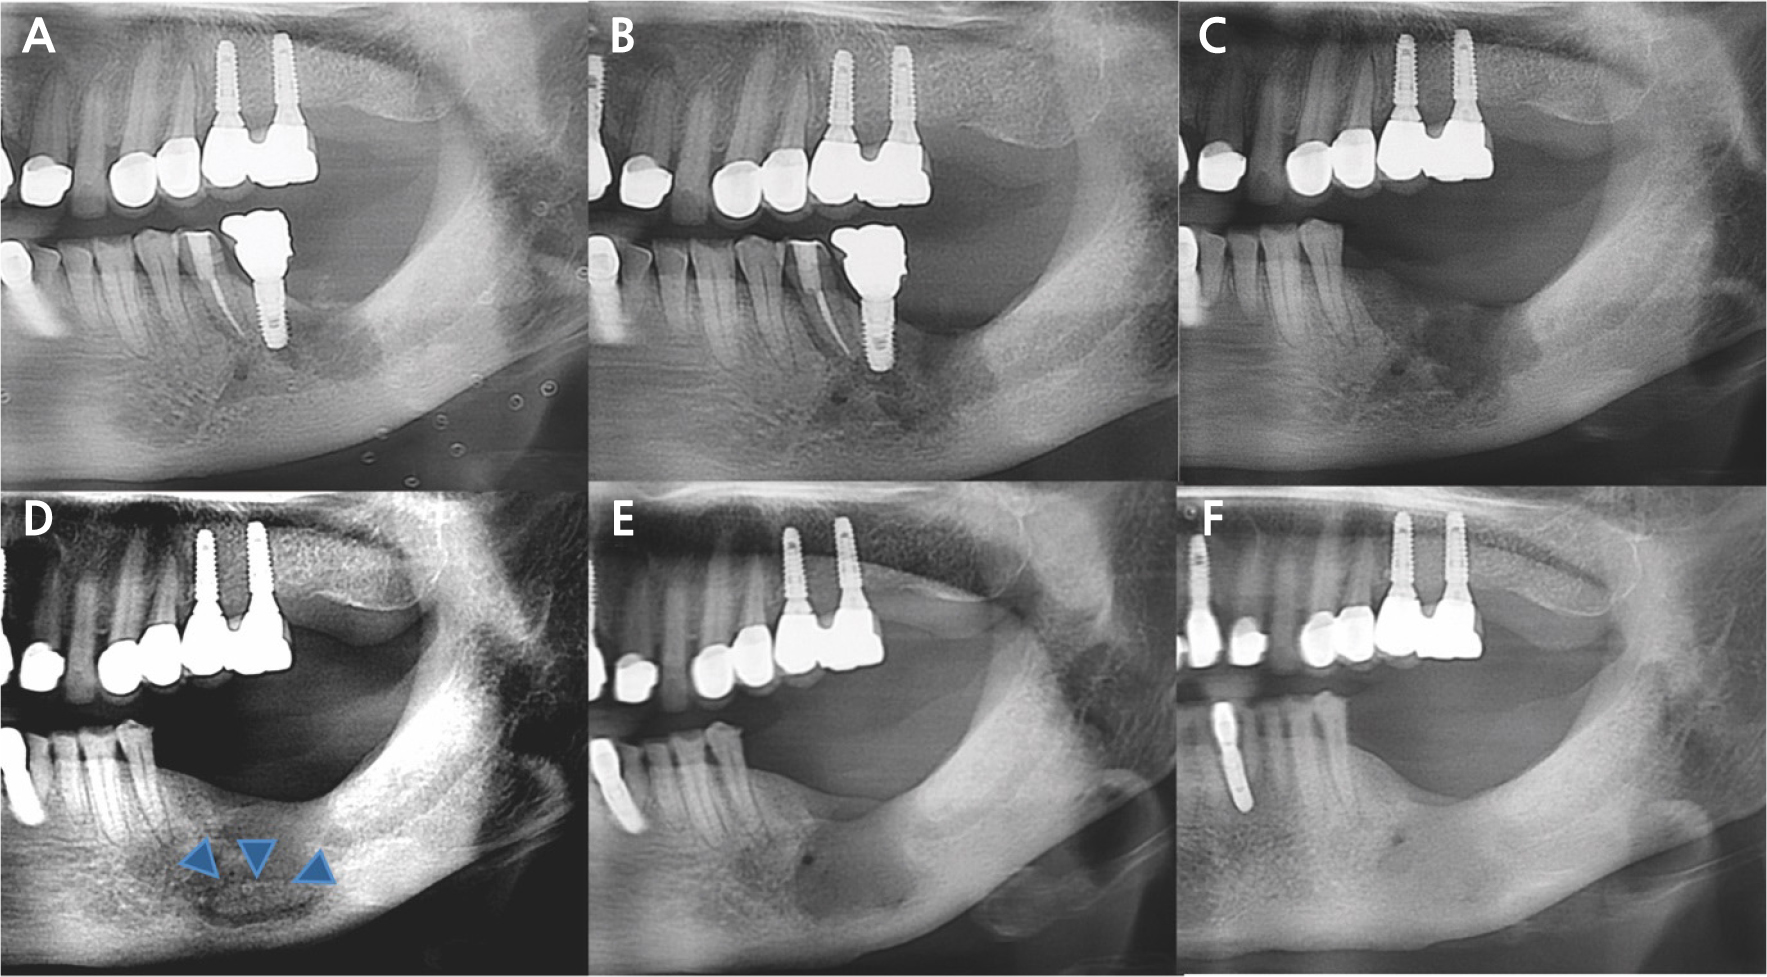

The patient developed persistent pain following osseointegration and prosthetic restoration. A panoramic radiograph revealed no significant lesions except for bone loss on the mesial side of implant #37 (Fig. 1). Despite multiple flap surgeries, the symptoms persisted. On November 26, 2015, implant #37 was removed in the Department of Periodontology at our hospital (Fig. 2A). As discomfort continued, she was referred to the Department of Oral and Maxillofacial Surgery on December 3, 2015, for further evaluation and management. Conservative treatment was attempted for 3 months; however, the lesion progressed, necessitating the extraction of implants #36 and #35 on March 4, 2016 (Fig. 2B and 2C). Six months later, sequestrum formation was observed (Fig. 2D). A sequestrectomy was subsequently performed, resulting in satisfactory healing of the left mandible (Fig. 2E and 2F). The patient discontinued Fosamax and was transitioned to Prolia (denosumab 60 mg, subcutaneous injection every 6 months) on June 2, 2021. Since then, she has continued to receive regular Prolia injections.

Fig. 2

(A) Implant #37 was removed in the Department of Periodontology, (B, C) The lesion worsened during 3 months of conservative treatment, leading to the extraction of implants #36 and #35, (D) Sequestrum formation was observed after 6 months (blue arrowhead), (E, F) Sequestrectomy was subsequently performed, resulting in satisfactory healing of the left mandible.